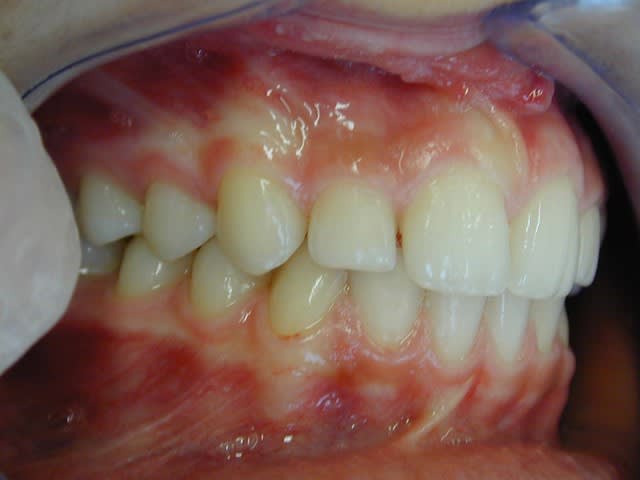

l'occlusion;

NB: Dans les 2 cas , pas de version des inc infs!